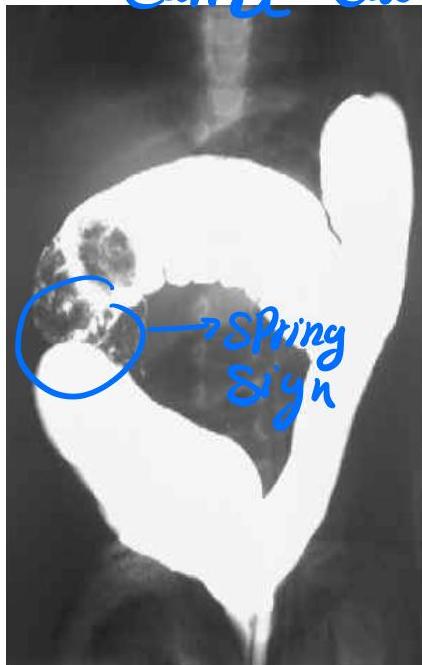

Hirschsprung Disease

describe x-ray

There is fecal impaction, transitional zone (dilated part proximally and constricted part distally)

Barium Enema Findings:

- Fecal impaction

- Transitional zone (dilated part proximally, constricted part distally)

- Narrow distal segment

- Dilated proximal segment

- Funnel-shaped dilatation at level of transitional zone

Causes:

- Absence of ganglion cells (aganglionic megacolon)

Presentations:

- Delayed passage of meconium

- Chronic constipation

- Toxic megacolon

- Signs of intestinal obstruction

Confirmation:

- Full-thickness rectal biopsy (to check for absence of ganglion cells)

Management:

- Resuscitation, NPO and IV fluids

- Antibiotics

- Rectal tube, irrigation

- At age 6-12 months: resection of aganglionic segment and anastomosing (formal pull-through procedure)